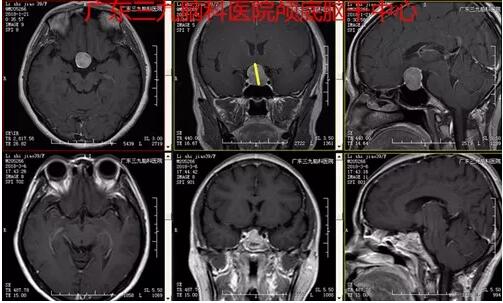

▲图3:术前MR示鞍区示一巨大占位性病变,T1WI呈略低信号,T2WI呈稍高信号,增强后呈明显强化,病变界限清晰,边缘光整,范围约为2.5×2.0×2.2cm。病变示明显束腰征,垂体柄受压显示不清,视交叉受压上抬。术前术后磁共振对比显示原肿瘤已切除。

▲图4:术后病理示(鞍区)垂体腺瘤